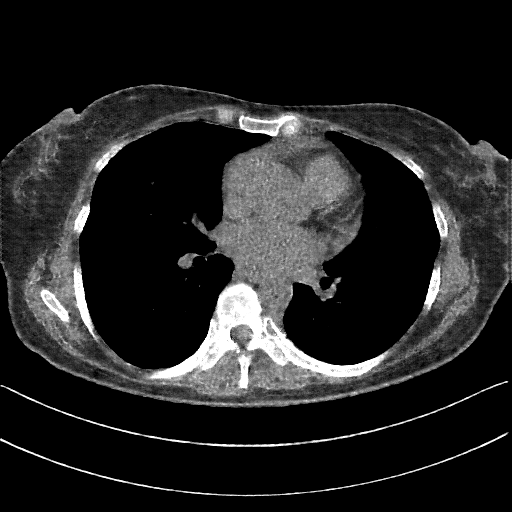

Image Grid

4×3 grid: Rows show different image types (Original NATIVE, Reconstructed NATIVE, Original VENOUS, Generated VENOUS), Columns show windowing techniques (No Window, Lung Window, Mediastinum Window)

Original NATIVE CT scan (input)

No window - Raw intensity values

Reconstructed NATIVE CT scan (cycle consistency)

No window - Raw intensity values

Original VENOUS CT scan

No window - Raw intensity values

Generated VENOUS CT scan (A→B translation)

No window - Raw intensity values